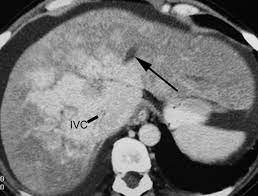

Chiasmata -mə-tə or chiasmas also chiasms 1. Esophageal varices are extremely dilated sub-mucosal veins in the lower third of the esophagus. Located in metro Denver northern Colorado and western Nebraska serving all of the Front Range our team consists of board-certified and fellowship-trained interventional radiologists. This results in hepatic congestion similar to Budd-Chiari syndrome and post-sinusoidal portal hypertension. The patients condition should be monitored throughout the procedure. They are most often a consequence of portal hypertension commonly due to cirrhosis. Toxic injury to liver sinusoids causes sloughing of endothelial cells that embolize to hepatic venules and cause eventual fibrosis of the venules. Coin in the Esophagus. There is no clear consensus regarding the number of occluded veins some authors claim that there should be at least one occluded hepatic vein 7 others state that there are no significant.

Carcinoma of the Colon. Budd-Chiari syndrome a blockage in one or more veins that carry blood from the liver back to the heart. And coumarin skin necrosis adrenal gland hemorrhage and infarction. Toxic injury to liver sinusoids causes sloughing of endothelial cells that embolize to hepatic venules and cause eventual fibrosis of the venules. Chiari malformation CM is a structural defect in the cerebellum characterized by a downward displacement of one or both cerebellar tonsils through the foramen magnum the opening at the base of the skull. Embolism and thrombosis of. La présence dune ou plusieurs affections prothrombotiques est fréquente La prise en charge repose sur un traitement anticoagulant précoce le traitement de l.